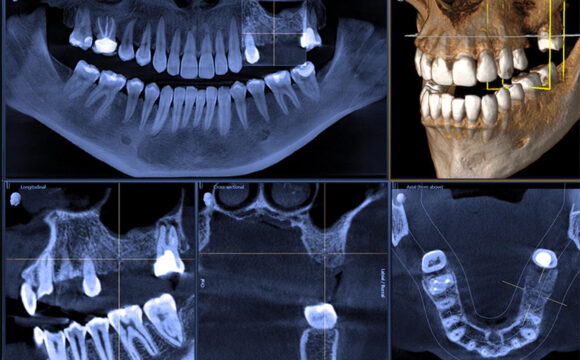

Po pierwsze w przeszłości kanały zębów leczono „na wyczucie”, bez powiększenia czy precyzyjnej diagnostyki. Kanały były niedoczyszczone, a przez to z czasem pojawia się stan zapalny. Dziś leczenie endodontyczne przeprowadza się z wykorzystaniem mikroskopu, co umożliwia dokładne oczyszczenie i wypełnienie kanałów.

Drugi powód to maszynowe leczenie kanałów. Wielu stomatologów preferuje ten sposób leczenia. W efekcie każdy kanał opracowany metodą maszynową wygląda tak samo. Nie jest to dobre podejście ponieważ KAŻDY kanał wymaga dostosowania do indywidualnego kształtu zęba – maszyna tworzy kanały okrągłe, a naturalne są często nieregularne. W efekcie po 5, 10 czy 15 latach taki kanał wymaga ponownego leczenia w powiększeniu.